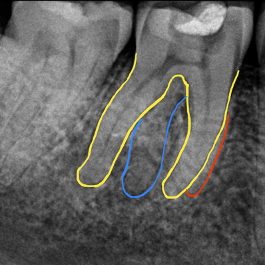

In radix entomolaris, the disto-lingual root often lies on the same bucco-lingual plane as the main distal root.

This superimposition can ‘hide’ the root, making it difficult to identify. Therefore, a parallax radiograph (taken from a 30 degree mesial or distal angulation) is helpful.

In a radix entomolaris, the main distal root (DB) may still have two canals (DB1 & DB2) (Figure 5). The DB2 is more difficult to locate and can be hidden in the isthmus between DB1 and DL. It is often in close proximity to DB1.

Use fine ultrasonics to conservatively open the isthmus to search for this canal (Figure 7).